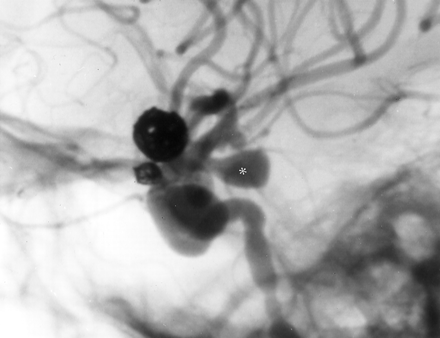

One hundred forty days after initial GDC treatment, the patient returned for elective treatment of her unruptured left posterior communicating artery aneurysm and the largest right internal carotid artery aneurysm. Angiography of the left internal carotid artery showed marked interval enlargement of the left posterior communicating artery aneurysm (Fig 2). It measured 6 × 10 mm compared with approximately 3 × 4 mm on an angiogram obtained during the patient’s initial treatment approximately 4.5 months earlier. The other aneurysms remained unchanged in appearance. The enlarged left posterior communicating artery aneurysm was successfully treated with GDCs with a steam shaped Prowler 14 through a 5F Envoy guide catheter. The contralateral carotid cave aneurysm was also treated. The patient tolerated this treatment without incident and was discharged in normal condition.

Four months after GDC treatment of the two ophthalmic segment aneurysms, lateral view angiogram of the left carotid artery shows marked interval enlargement of the posterior communicating artery aneurysm (asterisk, compare with Fig 1B). The treated ophthalmic aneurysms remain completely obliterated.